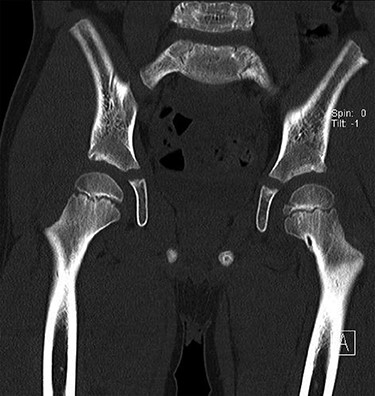

CT hips reported a well-defined lesion seen bilaterally in the neck of femur anterior infero-medial aspect, more prominent on the left side measuring 7 x 3 mm on left side both in coronal (Fig. 3) and axial (Fig. 4) views. On the right side, other lesion measuring 2 x 1 mm (Fig. 5) seen in coronal view. These two lesions are well defined with a sclerotic border with a small cortical defect. The lesion shows fat density. The symmetrical appearance of the lesion combined with the fat density and location suggest the diagnosis of synovial herniation pit. MRI Pelvis revealed minimal left hip joint effusion with loculated fluid seen along the trochanteric bursa with the largest measuring 0.9 x 1.5 cm (Fig. 6, 7).

Sowed coronal cut of CT hips demonstrating the synovial pit on left and right side.